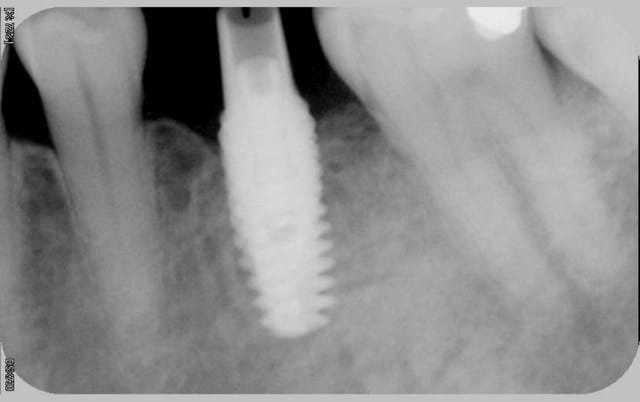

comme promis

voici les cas vus ce mardi (il me manquait encore 10 patients: sur les 5 autres, tout est ok)

ps: la carie et le tartre sur la 7 ont été traités